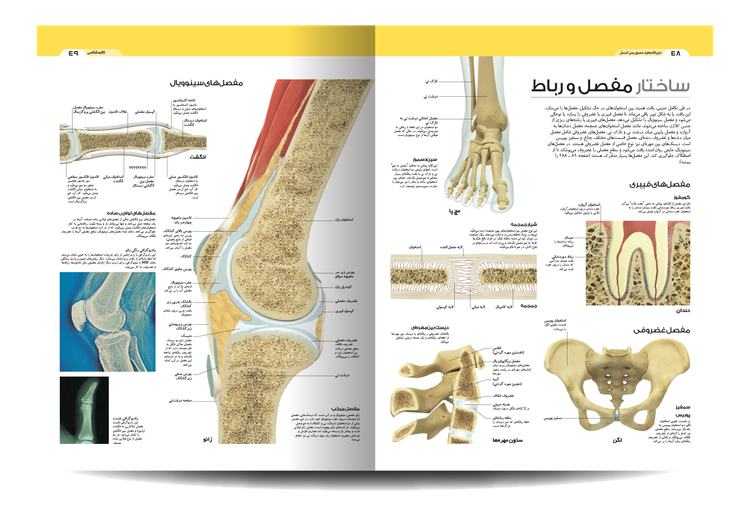

آناتومی زیبای ما را ببینید و نحوه عملکرد اسکلت، ماهیچه ها و رباط ها را بخوانید. این ویرایش دوم شامل جزئیات بیشتری در مورد مفاصل دست و پا است. کتاب «دایره المعارف مصور بدن انسان» شما را از دوران نوزادی تا پیری می برد و نشان می دهد که بدن ما چگونه رشد می کند و تغییر می کند و چه چیزی ممکن است اشتباه باشد.

این راهنمای تصویری از تصاویر و نمودارهای قابل توجهی برای نگاه کردن به بدن پیچیده و شگفتانگیز ما استفاده میکند. این در قالبی ساده و با توضیحات ساده نوشته شده است تا بهترین نمای کلی از بسیاری از چیزهایی را که ما را انسان میسازند به شما ارائه دهد.